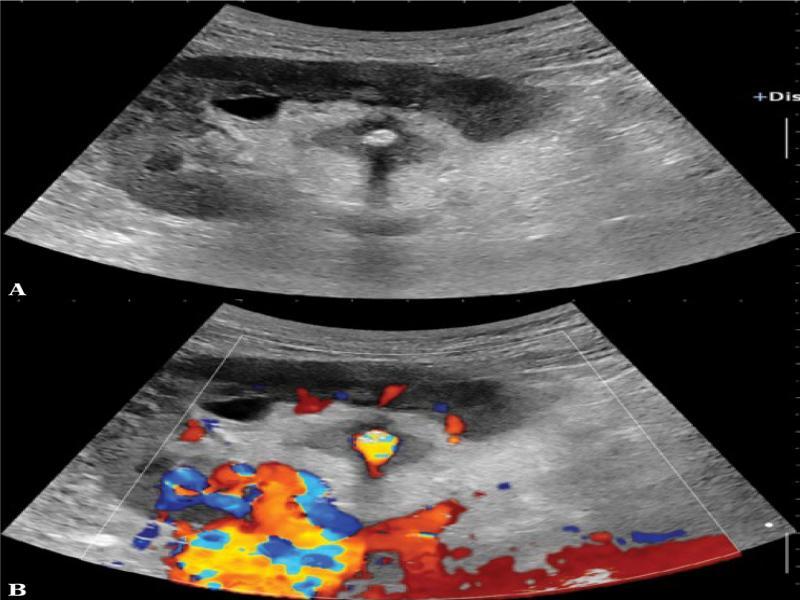

Fig. 1.